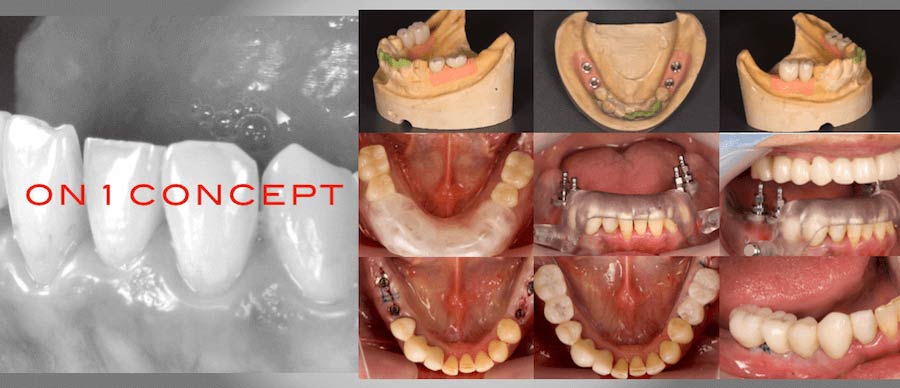

両側下顎臼歯部

両側下顎臼歯部は、ノーベルガイドを用いてインプラント埋入手術と同時に仮歯を入れ即時荷重を行った。その際、Nobel Biocare 社の ON1 CONCEPT を使用している。